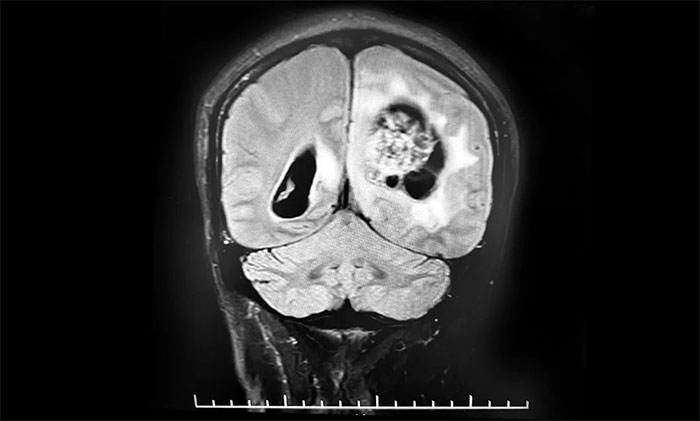

今年10月7日,患者突发意识不清,伴右手不自主抖动,呼唤有反应,反应迟钝,立即就诊于当地医院。行头颅增强MR提示:左侧额顶叶、胼胝体体部及压部、丘脑占位伴左侧顶叶占位,范围较前明显增大,均以弥漫性胶质瘤考虑伴左顶叶肿瘤卒中出血。10月11日,患者症状较前加重,出现嗜睡,反应迟钝,右侧肢体肌力明显下降。当地医院表示无法救治,希望渺茫。

头颅MRI平扫+增强+DWI+MRA提示,左侧顶枕叶巨大肿瘤伴局部瘤卒中,幕上脑室系统、脑干受压变形,中线结构右移19mm,大脑镰下疝形成。李士其教授等专家团队会诊指出,患者脑内巨大占位,性质不明,并且患者已经发生脑疝昏迷,生命危在旦夕,应尽快进行手术治疗,挽救患者生命,同时明确病理诊断。

▲ 左侧顶枕叶巨大肿瘤伴局部瘤卒中